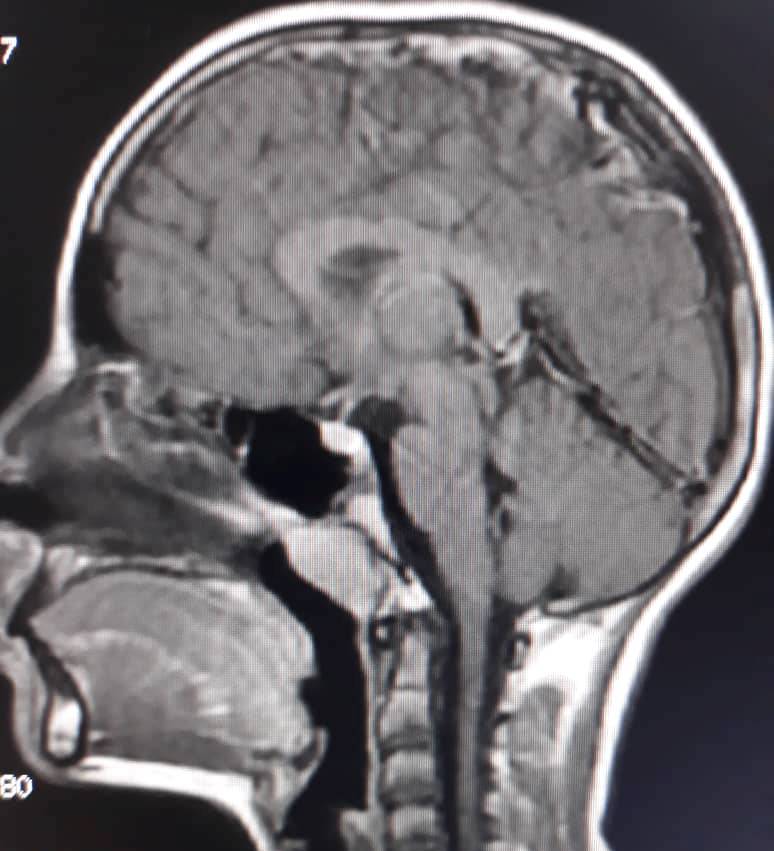

وأضاف :تم رفد العيادة العصبية بجهاز تخطيط دماغ وجهاز تخطيط جذع دماغ، يؤمن للمرضى التشخيص المناسب وهو قيد التشغيل والتجربة ليوضع في الخدمة قريباً، وبجهاز تنظير هضمي علوي وسفلي وجهاز تصوير بالطرق الراجعة ERCP وهو قيد الافتتاح.